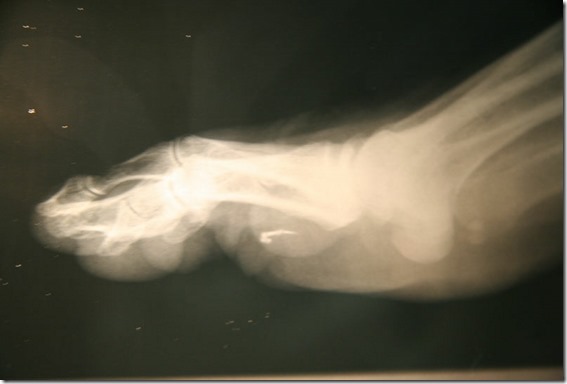

Roger Leir, podólogo da Califórnia, também afirma ter removido implantes alienígenas dos pacientes.

Os objetos são encontrados frequentemente nas extremidades, como pés, mãos e pernas. Nickell cita a opinião do Dr. Virgílio Priscu, chefe de departamento ensino hospitalar de Israel que afirma: "sem mistério, sem implantes", explicando que objetos são resultados de quedas ou por andar descalço muitas vezes acabam rodeado por tecido cicatricial.

No entanto, tais dispositivos têm sido detectados através de métodos convencionais, tais como raios X e ultra-sonografia. Existem ainda relatos de pessoas que ficaram extremamente doentes após a remoção cirúrgica dos implantes alienígenas.